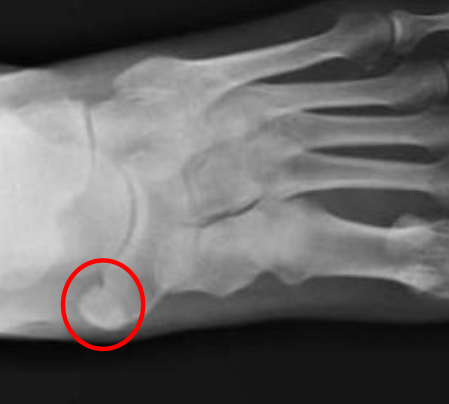

Algunos de ellos son relativamente frecuentes y confunden sus síntomas con fracturas. Pueden producir dolor en la zona y limitación de la articulación o miembro. En las imágenes vemos un OS NAVICULAR o escafoides accesorio.